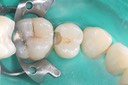

Mark Chun #2 pre-op

Mark Chun #2 caries removal

Mark Chun #2 prep